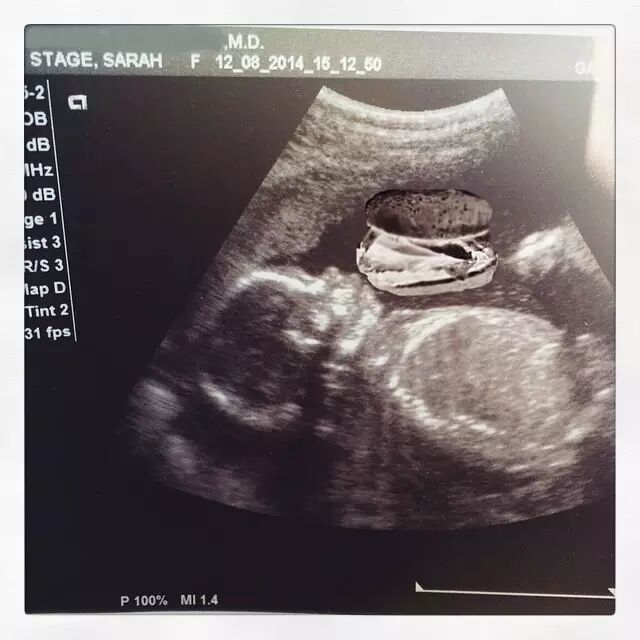

这是她娃的B超,医生表示她的宝宝很健康,大概已经有5磅重了。